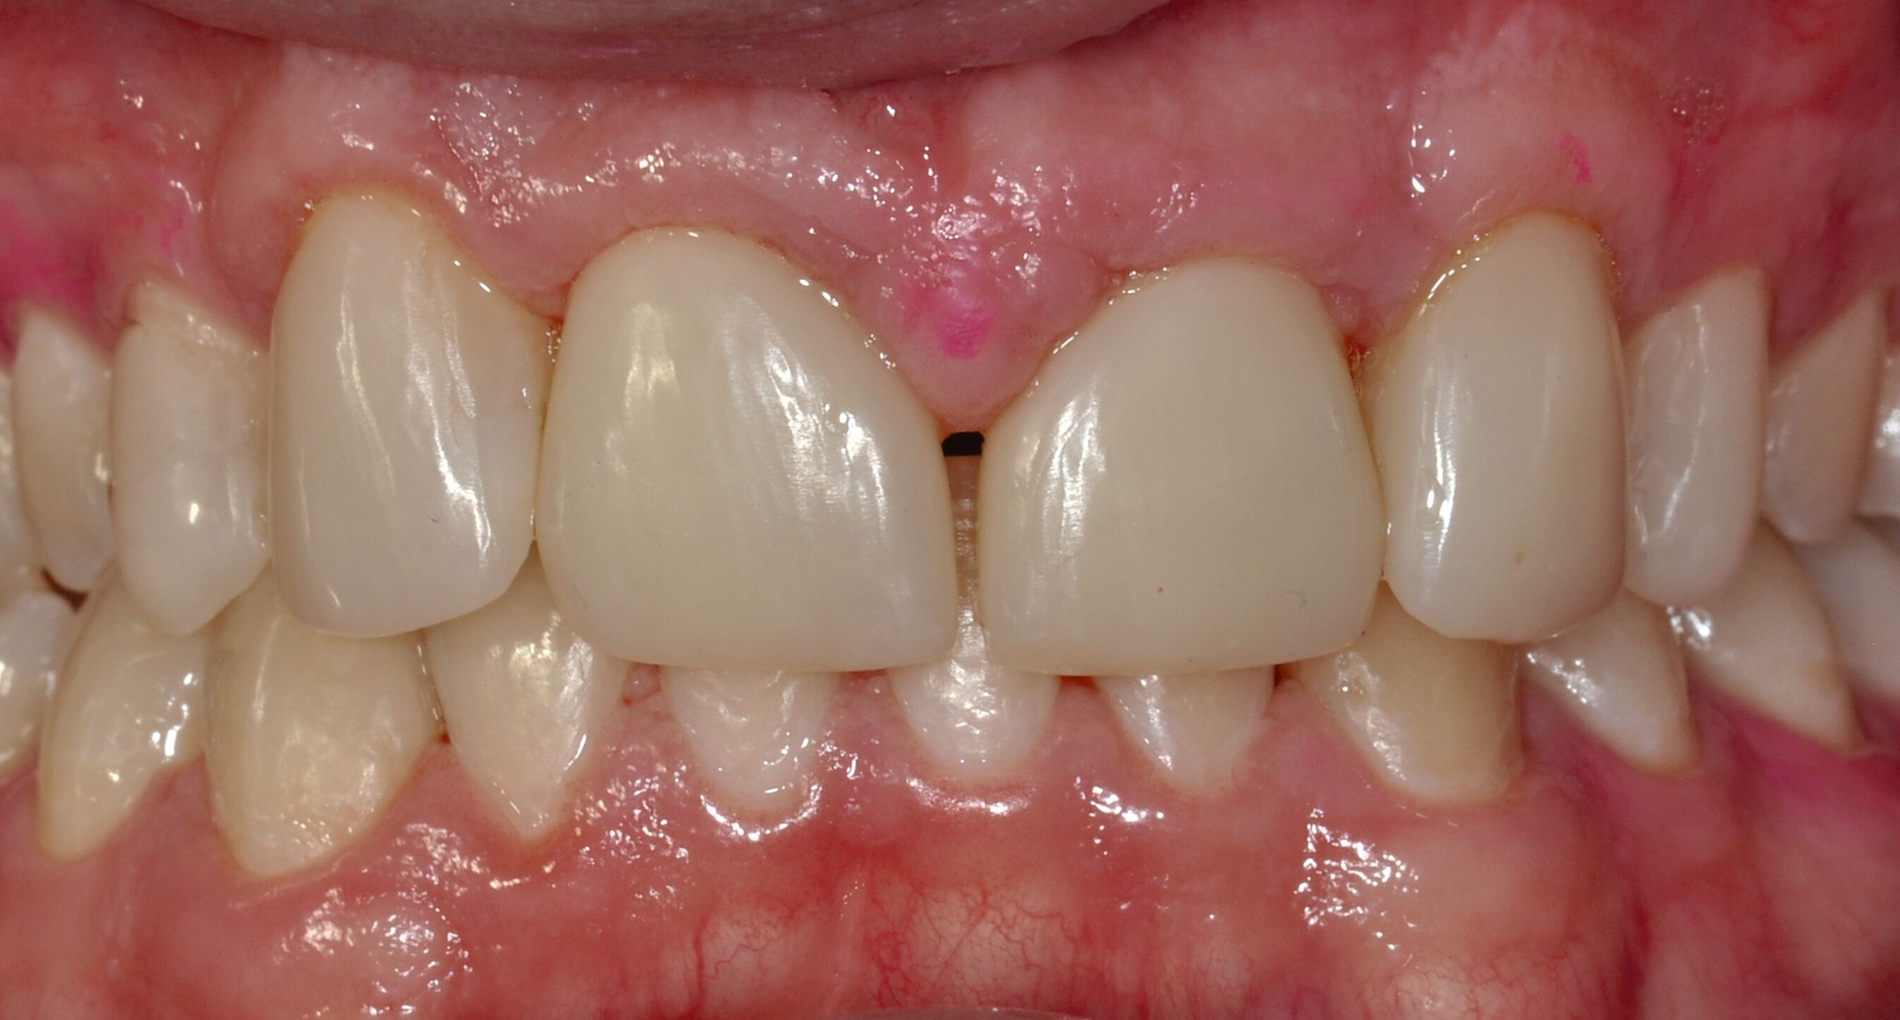

Auch bei einer Kontrolluntersuchung drei Jahre nach restaurativer Therapie sind die Versorgungen in situ, intakt, und das Parodontium zeigt keine entzündlichen Veränderungen. Trotz Anfertigung der Retentionsschienen fällt ein beginnendes Diastema mediale auf (Abbildung 4). Der Patient gibt auf Nachfrage an, die Schienen nicht regelmäßig getragen zu haben. Ihm wird die Möglichkeit eines Diastemaschlusses durch eine erneute Zahnformkorrektur angeboten. Da ihn die entstandene Lücke jedoch subjektiv nicht stört, entscheidet er sich zunächst gegen eine restaurative Korrektur.